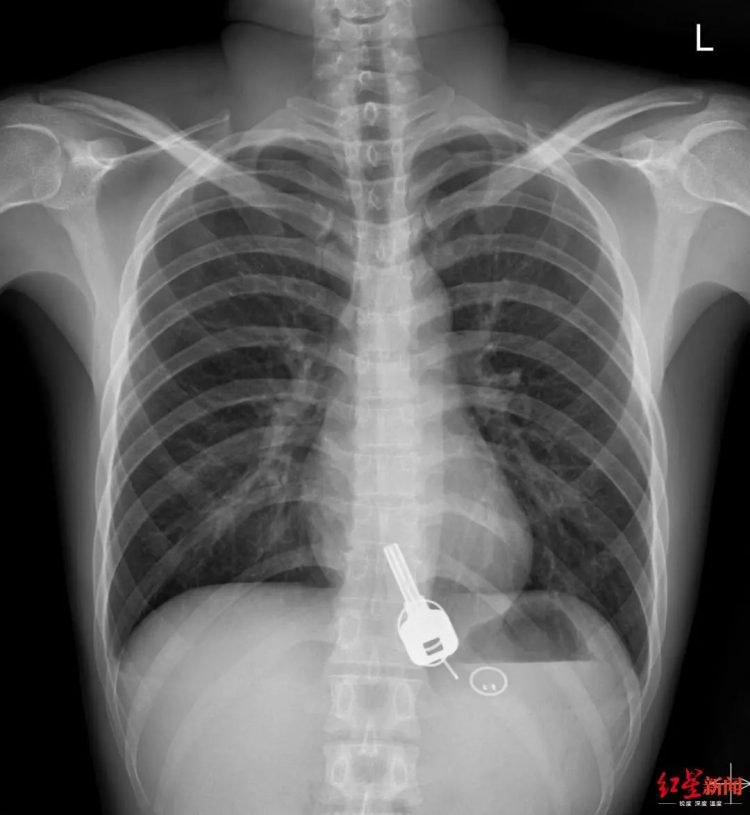

Khi chụp X-quang cho Chang, bác sĩ sốc khi thấy một vật trong giống chiếc chìa khóa trong thực quản của nam thanh niên. Khi hỏi Chang, anh này thừa nhận làm mất chìa khóa nhà vào đêm hôm trước nhưng không thể giải thích vì sao vật này lại ở bên trong cơ thể mình.

Chiếc chìa khóa nằm trong cơ thể của bệnh nhân Chang theo ảnh chụp X- quang. Ảnh: Sohu